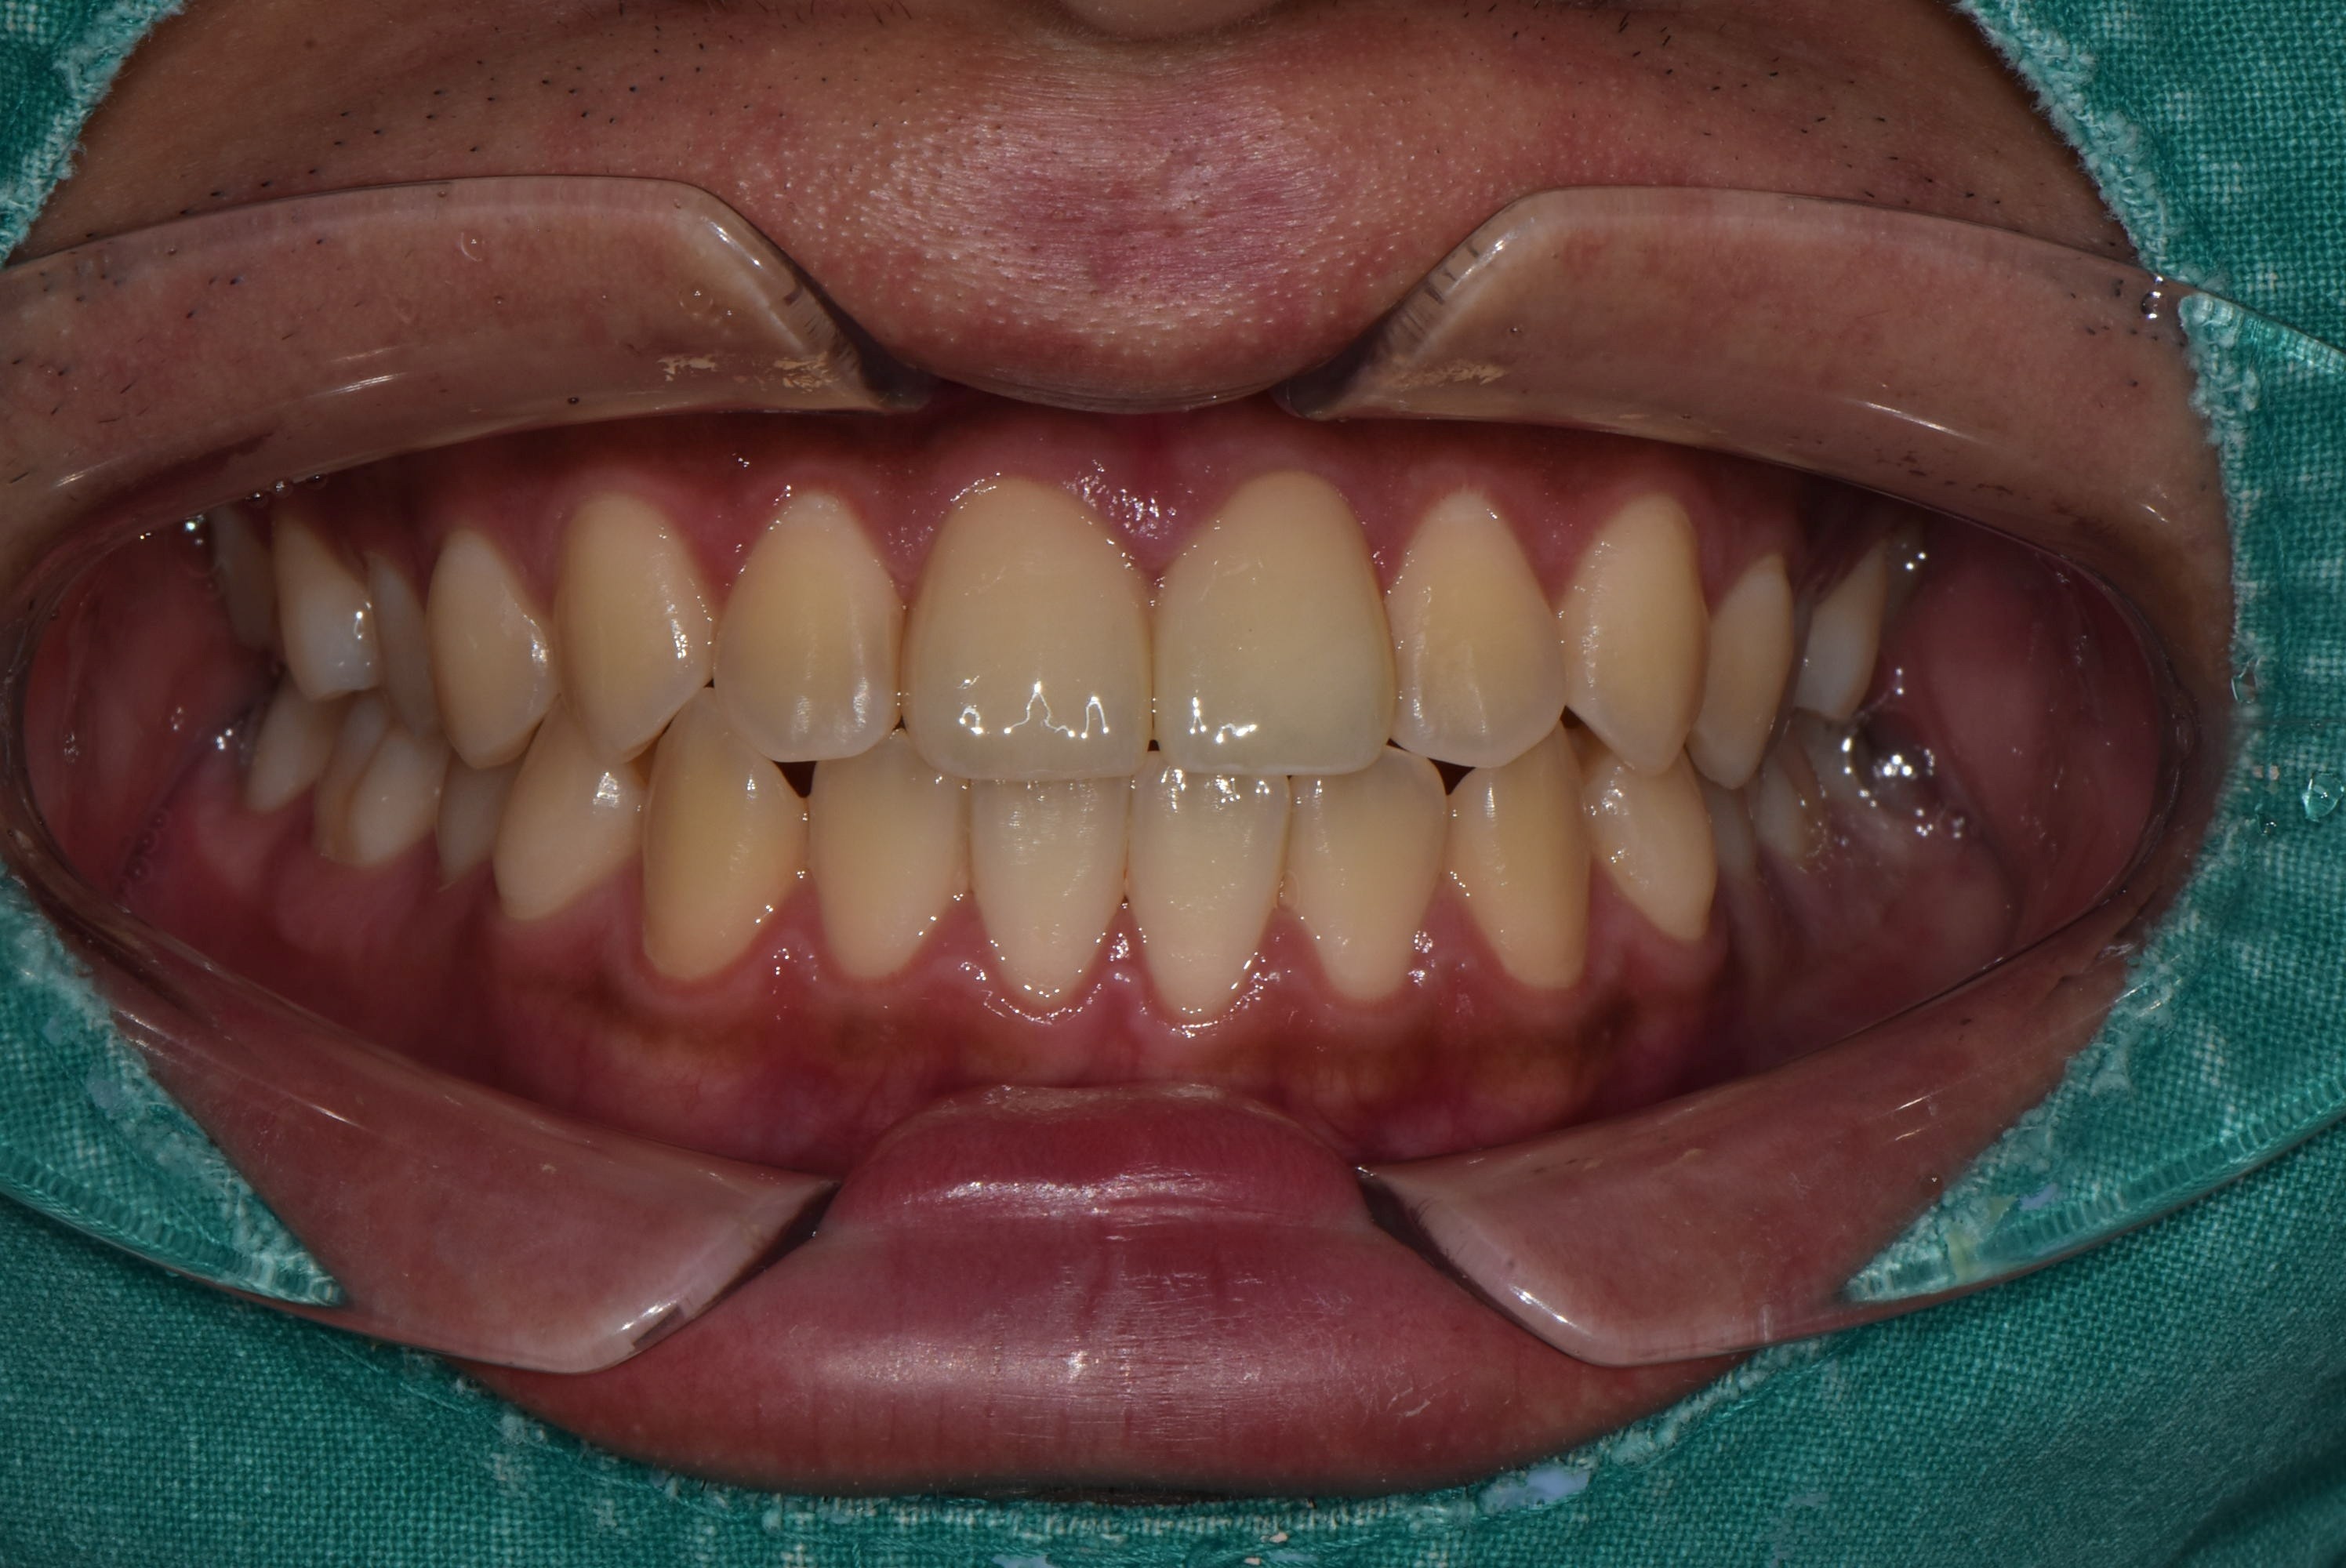

After 25.09.26

약 1주일 후,

보철이 엄청 자연스럽게 완성되었어요!

완전 내 치아처럼 자연스럽죠?

신곡동치과 두번의 내원만에 치료가 완료 되었습니다 !! ^.^

충치 치료는 물론 심미적으로도 더 아름다워 졌네요 ^^